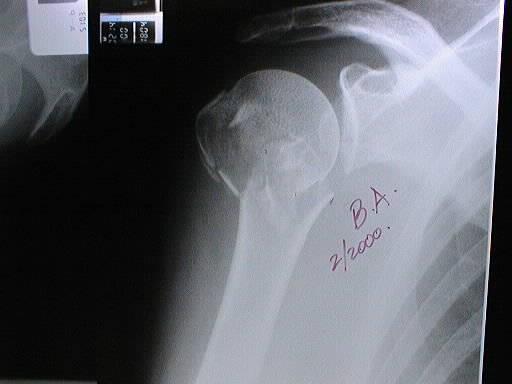

PRE - OPERATORIO

B1